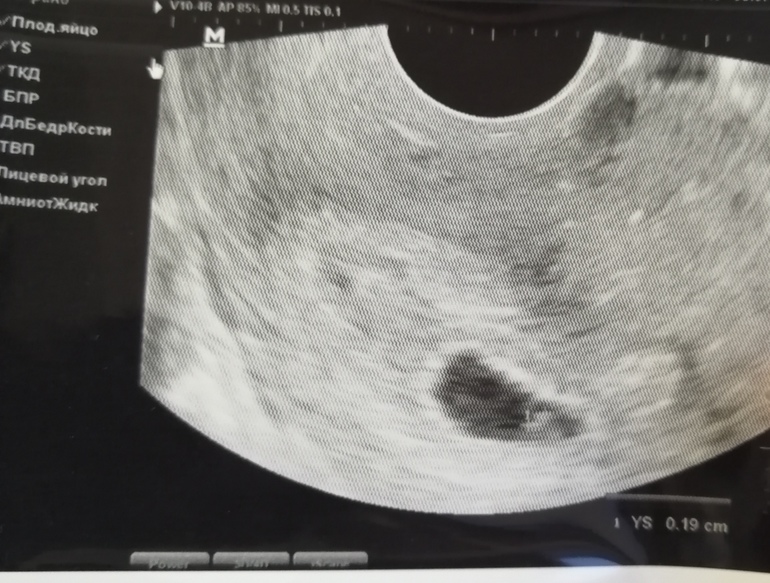

ФолликулометрияБыла на узи, надеялась увидеть эмбриона, увидели только плодное яйцо 1,58 см и сказали что срок беременности 5+3.

На сроке 5+6 у меня не увидели эмбриона, даже желточный мешочек не увидели, потом в конце узи что-то зафиксировали в углу, прям как у Вас. Так что, на мой взгляд, ничего страшного пока не произошло, особенно, если имплантация была на пару дней позже. Фото узи на 5+6 прилагаю.